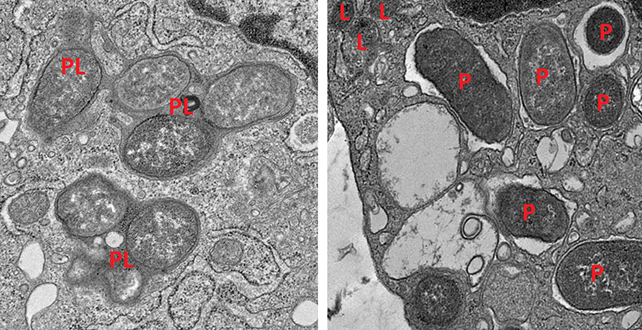

Tracking the behavior of immune cells called macrophages through the expression of their genes, the researchers discerned which cells helped the gut stay healthy and which became inflammatory and caused damage.

Macrophages in the gut can switch between two states, one for attacking infection (inflammatory) and one for repairing damage (non-inflammatory). It’s been well established that keeping these two states balanced is important for a healthy gut.

One gene found to promote the non-inflammatory macrophage mode produces a protein called girdin. It turns out that the girdin and NOD2 proteins work together to ensure macrophages remain alert to threats, but not overly reactive. Without them, macrophages in repair mode are less efficient at cleaning up targets, while those in attack mode are overly inflammatory.